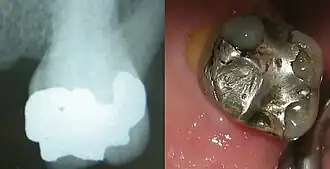

Amalgame dentaire

En dentisterie, un amalgame dentaire est un matériau utilisé pour obturer les cavités résultant de l'élimination de tissus dentaires affectés par des caries.